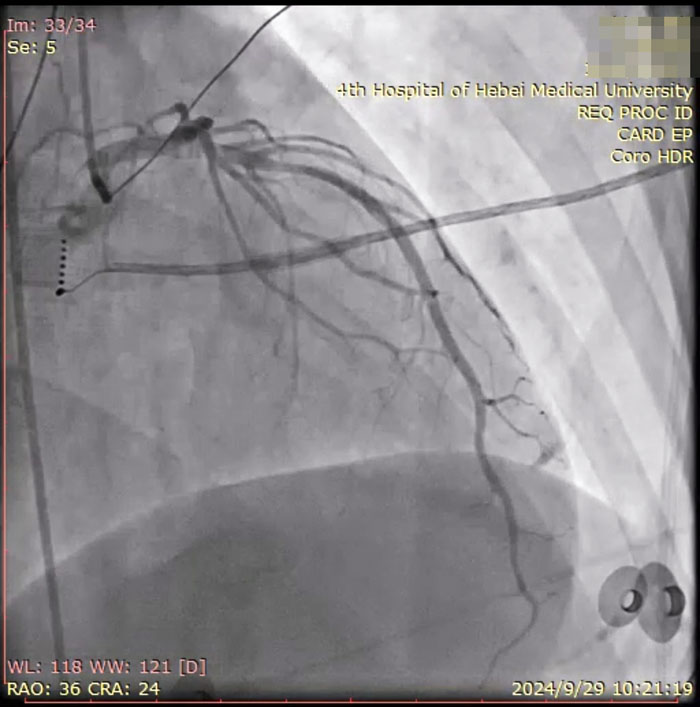

手術當日,醫護人員連接多導電生理儀和CARTO三維標測系統,對病人進行術前消毒,局麻后穿刺股靜脈,操作ST消融導管至右房,建立右心三維解剖。術中,姚鐵柱副主任操作ST消融導管經三尖瓣進入右室流出道,于右室流出道后游離壁標測到最早激動靶點,誘發室早形態與原體表心電圖室早形態相同,給予放電消融,患者室早消失;繼續行冠脈造影術,導管造影結果顯示,前降支中段可見約50%局限性狹窄。術畢,患者安返病房,心電圖示為“竇律規整”;繼續給予心電監測,患者無室早出現,心慌、氣短癥狀消失。根據冠狀動脈造影結果對其調節藥物治療,患者胸痛、背痛癥狀得到緩解。術后僅不到兩日,患者便順利出院。

術中患者冠脈造影